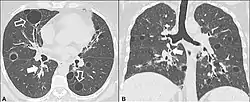

| CT scan of the lung showing bullae in the lower lung lobes of a subject with type alpha-1-antitrypsin deficiency. There is also increased lung density in areas with compression of lung tissue by the bullae. | |